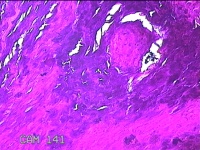

左侧足底结节

性别

男

年龄

49岁

临床诊断

鸡眼

一般病史

发现左侧足底结节伴隐痛不适1年余。

标本名称

大体所见

灰白粉红色带皮肤样结节1x0.7x0.2cm一个,表面糜烂,切开结节呈实性,切面灰白粉红色,质硬。